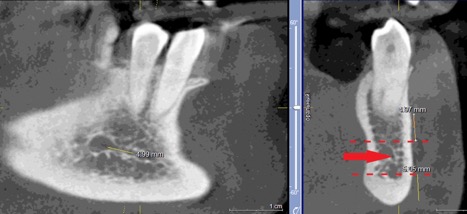

При измерении расстояния от резцовой петли до вестибулярной стенки нижней челюсти и её топографии в области правила «трёх пятёрок», выделено три положения канала, в котором проходит резцовая петля: канал прилежит, т.е. стенка канала образована кортикальной частью (рис 3), касается, т.е. имеет одну общую точку (рис 4) и не имеет общих точек.

Рисунок 3. КЛКТ Сагиттальныи и коронарныи реформаты переднего отдела нижнеи челюсти..jpg

Рисунок 3. КЛКТ Сагиттальный и коронарный реформаты переднего отдела нижней челюсти.

Стенка канала образована кортикальной частью кости.

Красная стрелка – «резцовая петля».

Красный пунктир – канал проходит в проекции участка правила «трёх пятёрок».